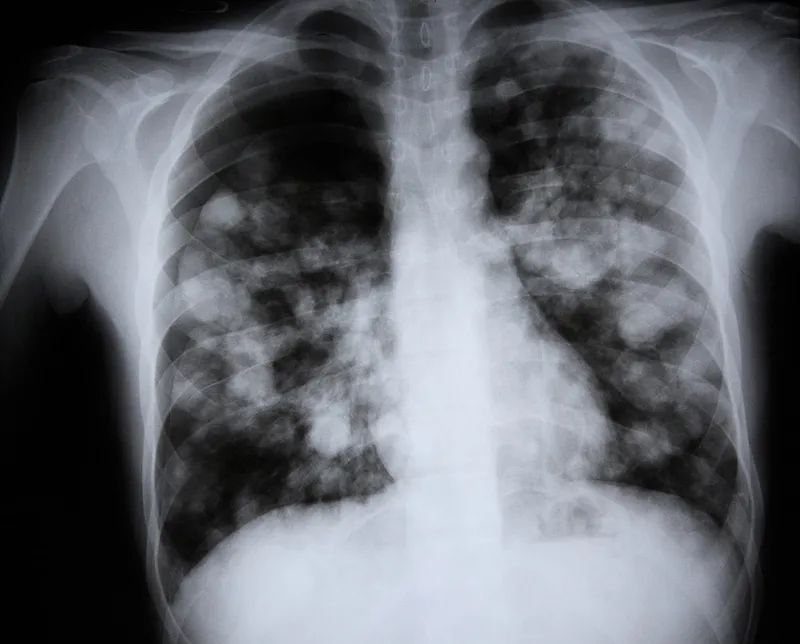

前段时间,今年52岁的朱先生因“胸闷气促7天”到医院就诊,诊断为甲流。

可经过一番治疗后,病情却不见好转,反而进一步加重,患者被紧急转至上海交通大学医学院附属瑞金医院嘉定院区急诊就诊。

入院时,朱先生的病情非常危重,持续高热、急性呼吸衰竭、电解质紊乱、休克等,在抢救室紧急气管插管后,急诊科陆一鸣主任当机立断将患者紧急收入急诊重症监护室接受进一步治疗。

病人体重近300斤,当时血压在大剂量升压药物维持下也只有60/40mmHg,心跳高达150次/分,全身花斑,四肢湿冷,血糖22mmol/l,血气分析pH:6.9,提示严重酸中毒(正常值7.35~7.45),休克。

针对如此危重病情,主治医生迅速抓住当前主要关键点:糖尿病酮症酸中毒,感染性休克,甲型流感病毒性肺炎等,并启动目标导向性液体复苏,控制血糖,连续性血液肾脏替代治疗(CRRT),调节酸碱平衡等综合治疗。同时进行脉搏指示连续心输出量监测(PICCO)和床旁心脏超声,监测心功能及指导液体复苏。

经过急诊重症监护室医护团队初步治疗,朱先生的酮症酸中毒、感染性休克有好转迹象,但患者病情仍然不容乐观:如何控制重症肺炎和急性呼吸衰竭等成为主要矛盾。

陆主任在仔细分析病情和影像学检查后,高度怀疑朱先生可能合并侵袭性肺曲霉病感染,立即安排行床旁纤维支气管镜检查及肺泡灌洗液查病原体,终于揪出“真凶”——流感相关性肺曲霉病(IAPA),随后立刻针对该患者调整治疗方案,启动抗霉菌治疗。

在急诊重症监护室经过近1个月的治疗后,朱先生病情逐渐稳定下来,并康复出院。